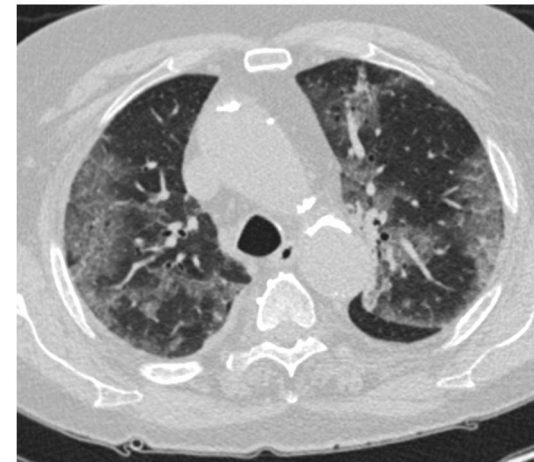

Paziente maschio 75 anni. Anamnesi remota muta, non comorbidità. Esordio con...